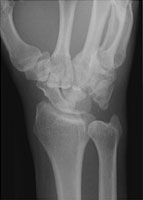

- Click on the image for a larger versionCOblique radiograph of the wrist. This shows the abnormal carpal bone relationships.